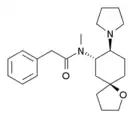

| Opioid peptides | Skeletal molecular images |

| DAMGO |  |